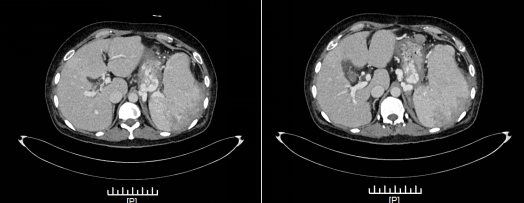

术前胃底大量曲张血管,脾脏增大,侧枝循环形成,胃肾分流。

手术过程惊险连连:7:00,苗春木医生带领介入团队对其行脾动脉栓塞术。术中造影可见脾动脉明显增粗,不断为脾脏输送大量血液;同时因为脾静脉闭塞,脾脏淤血,导致脾脏体积增大,脾脏血液只能通过侧枝的胃底曲张静脉回流。苗医生不得不使用了6枚弹簧圈和粗大的明胶海绵,苦战一小时,才彻底栓塞脾动脉。